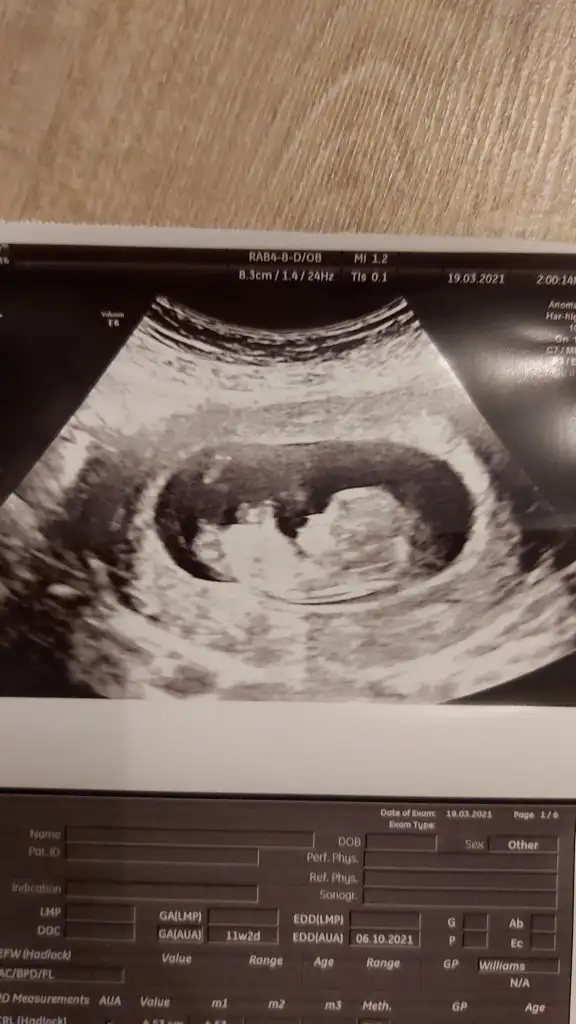

Banada bakar mısınızBen tahmin ediyorum 11 yada 12 hafta usg paylaşıyorsunuz nubu uygunsa görebilirsem tahminim dogru oluyor![]()

Evet kız görünüyor11 haftalık banada tahmin yapar mısınız arkadaşlar doktor %70 kız dedi sizce nedir . 1oğlum var buda kız olursa çok mutlu olurum

Eki Görüntüle 2806425

Teşekkür ederim cevap için. Hadi inşallahEvet kız görünüyor![]()